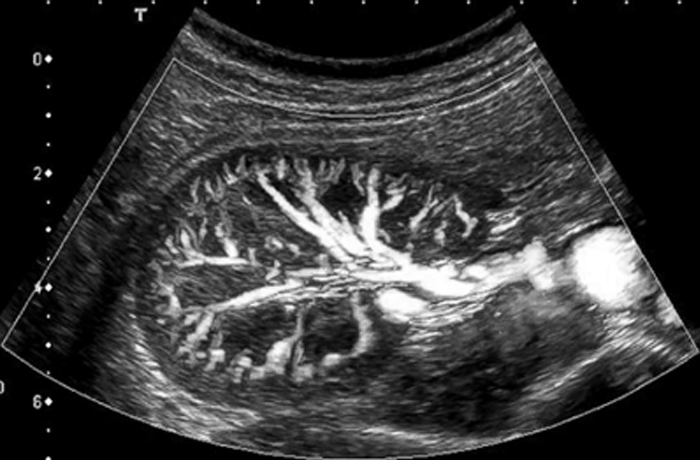

Ультразвуковое исследование артерий почек

УЗИ почечных артерий представляет собой высокоточный диагностический метод, который способен дать исчерпывающую информацию о качестве кровотока и структурных нарушениях кровеносных сосудов почек. Направить на это исследование может врач-терапевт, уролог, нефролог и др.

Процедура проводится следующим образом: врач наносит на кожу гель для улучшения проводимости ультразвука, а после начинает водить датчиком, в результате на монитор выводится изображение исследуемых сосудов. Заключение врач выдает уже через 20 минут после проведения исследования.